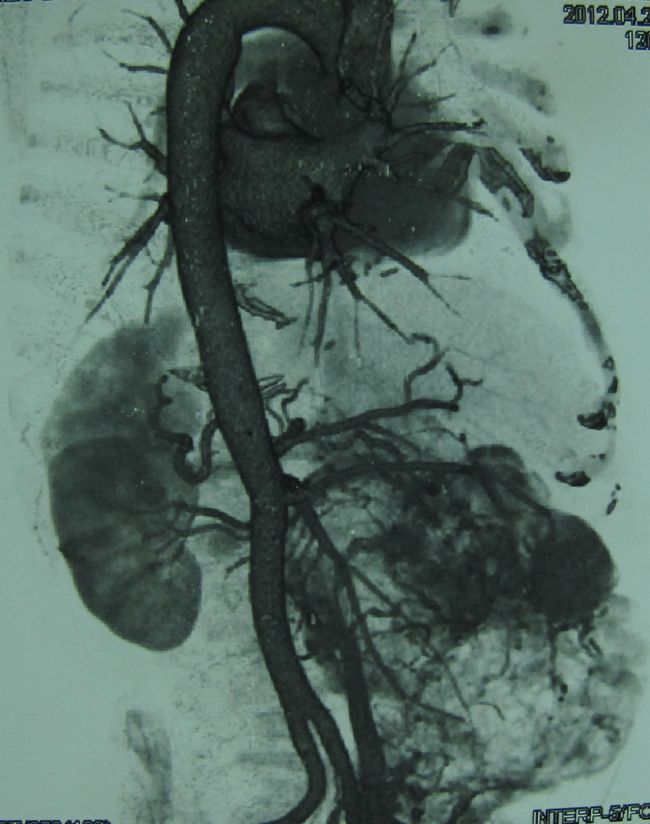

Опухоль правой почки (компьютерная томография с сосудистым контрастированием)